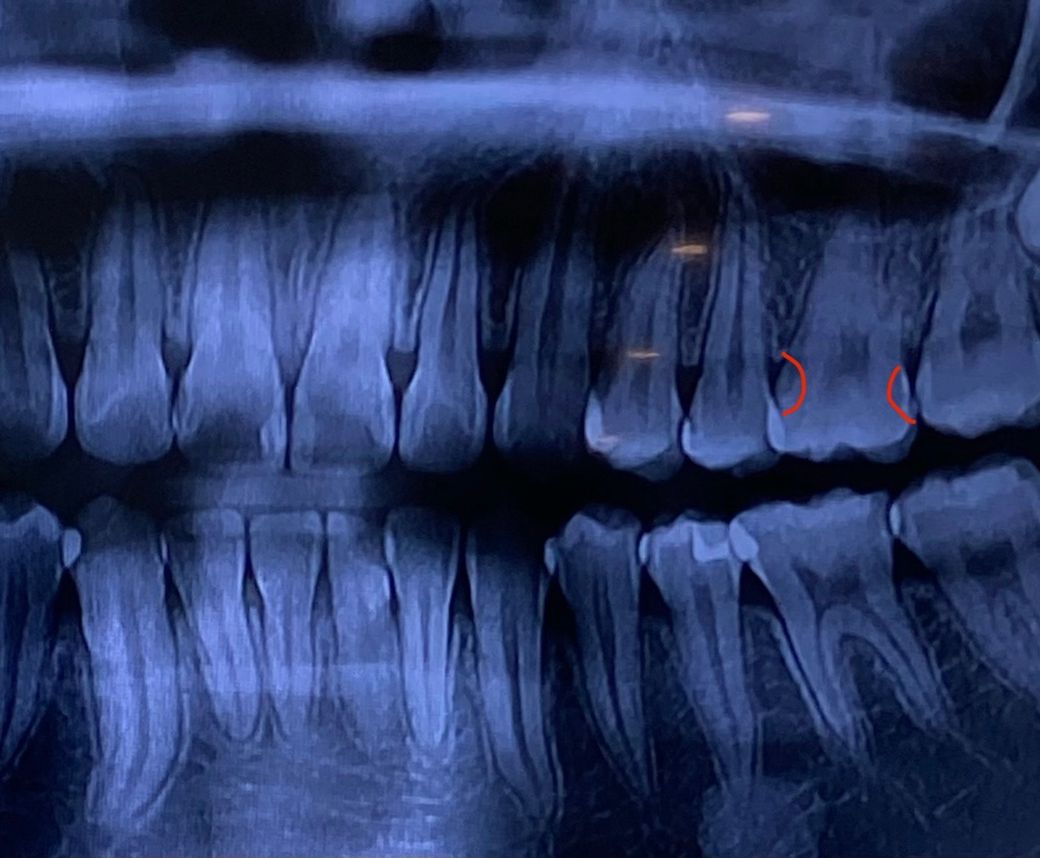

• 2번 째 사진

2. 엑스레이상 충치가 보입니다

3. 레진으로 해도 기구 접근을 위해 교합면 일부 삭제는 불가피합니다